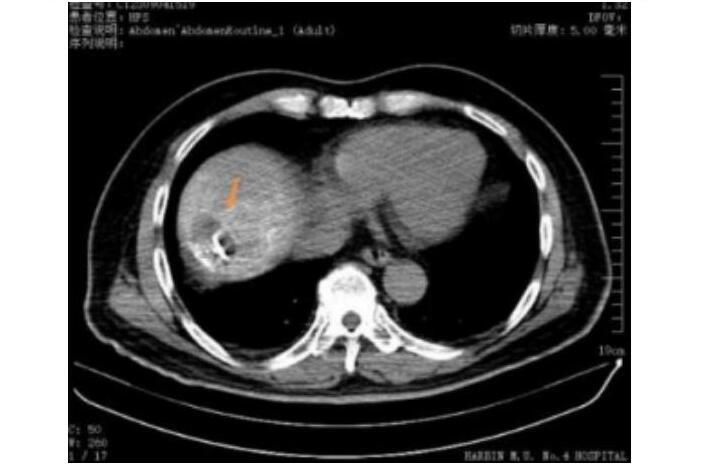

碘化油示踪小病灶准确穿刺消融

TACE联合射频消融